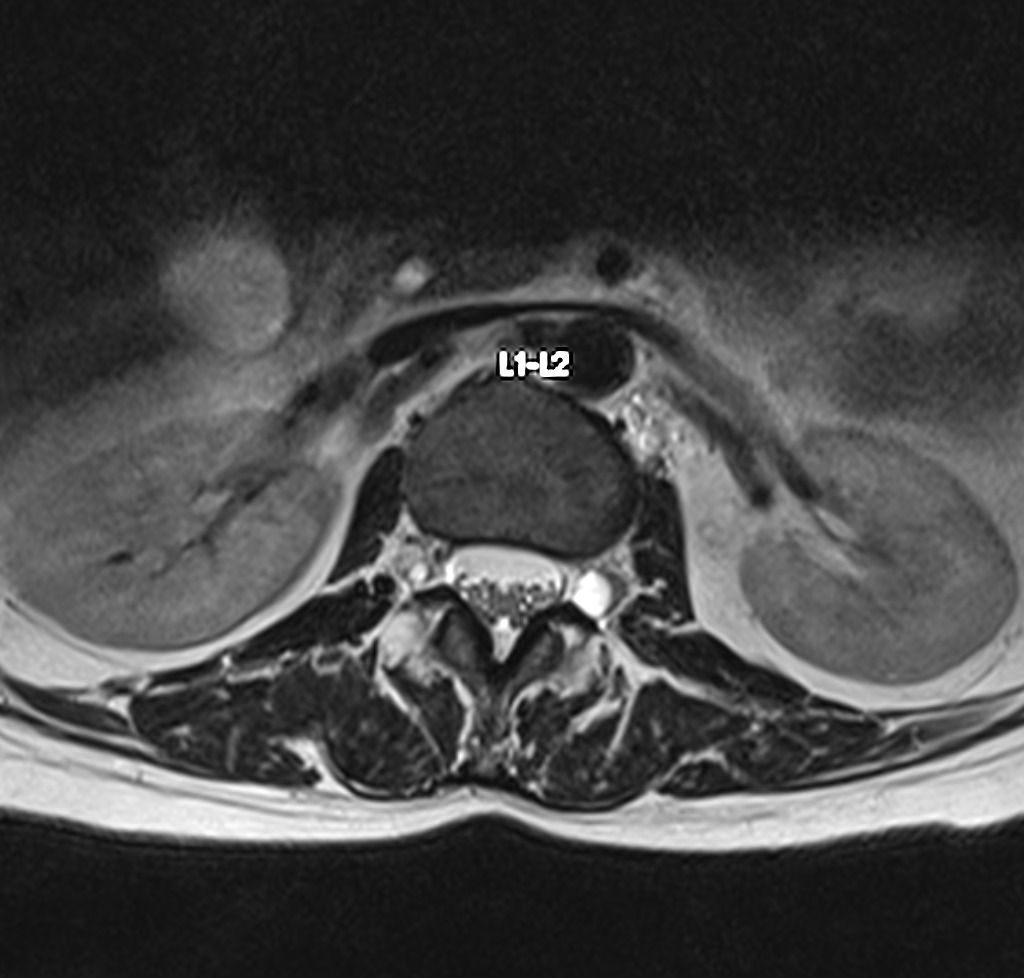

Resonancia Magnética de columna lumbar

“QUISTES PERINEURALES”

Los quistes perineurales son quistes llenos de líquido cefalorraquídeo en las raíces nerviosas, localizados principalmente en la zona sacra de la columna vertebral, aunque pueden encontrarse en cualquier sección de la columna vertebral; pueden causar una radiculopatía progresivamente dolorosa. Las mujeres se ven afectadas con mayor frecuencia que los hombres. Los pacientes con quistes perineurales presentan dolor en la zona de los nervios afectados por el quiste, debilidad muscular, dificultad para sentarse durante periodos prolongados, pérdida de la sensibilidad, pérdida de reflejos, dolor al estornudar o toser, inflamación en la zona sacra, parestesias, dolor de cabeza, ciática, y disfunción intestinal, de vejiga y sexual.

El diagnóstico se basa en la resonancia magnética.